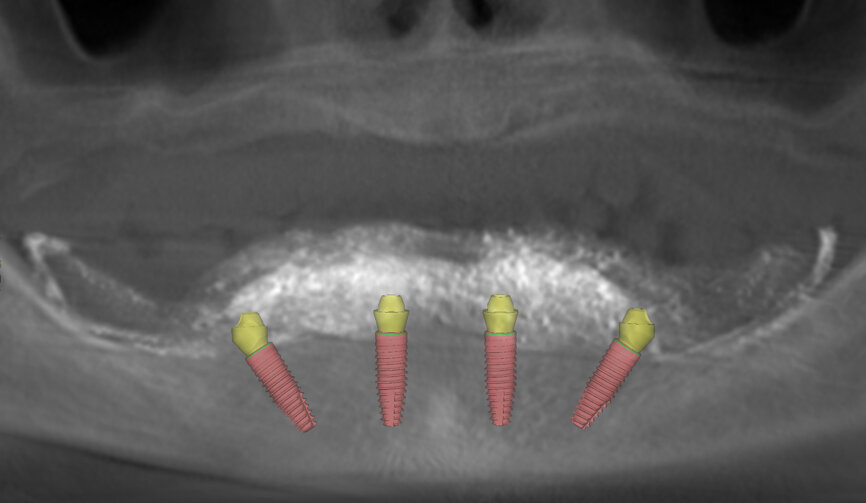

Bone quality in the mandible allowed placement of four implants in the anterior region, with both lateral implants tilted, and did not allow for any implants to be placed in the distal area. For these reasons, the Pro Arch concept was chosen as a treatment modality. As bone conditions in the mandible were very difficult in terms of correct implant placement, it was decided to place them with the help of a surgical guide.

The planning included several steps. First, the hopeless teeth in the mandible were to be extracted, followed by delivery of a complete immediate denture, as they did not offer any stable support for a surgical guide. Six weeks later, owing to the lack of keratinised tissue in the premolar regions, apical repositioning and a free gingival graft were performed (Fig. 2). After 1.5 months, the denture was relined with a mixture of barium sulphate and resin, transforming the denture into a radiographic stent (Fig. 3). Another CT scan was recorded with the stent in the mouth (Fig. 4). The stone cast of the stent was poured (Fig. 5), giving us the actual clinical picture of the mucosa, and both cast and stent were scanned to obtain their STL files. Using the coDiagnostiX planning software, the radiopaque saddle of the stent and the STL scan were matched, which also allowed the stent to be matched with the cast as positive and negative, thus, giving us the soft-tissue volume. Implants were planned in a prosthetically driven manner at sites #34, 32, 42 and 44, with corresponding screw-retained abutments (Fig. 6).

Because of an open-flap procedure owing to the lack of keratinised tissue and the placement of long implants (all Straumann BLT Roxolid, SLA implants; 4.1 × 12.0 mm), it was decided to make two surgical guides: first, a mucosa-supported guide only for drilling the template fixation pins (Straumann; Fig. 7); and second, a pin-supported guide for fully guided implant placement (Fig. 8).